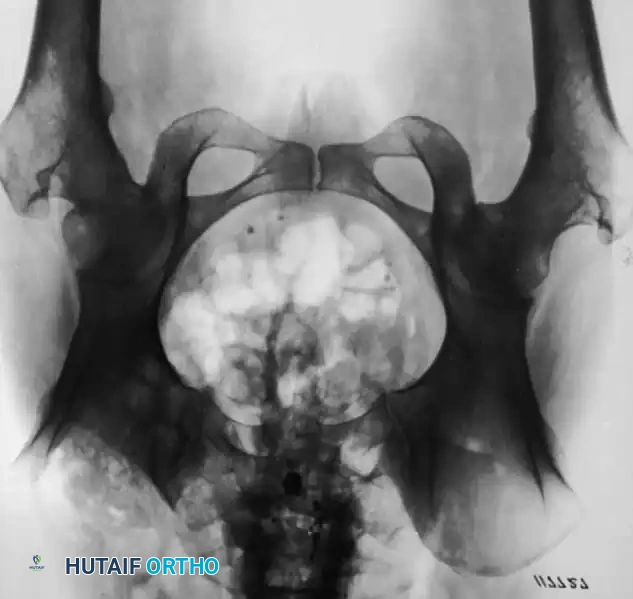

Fig. 16-21 A, Sliding abdominal hernia and osteomyelitis of the right iliac crest after the removal of a bone graft for fusion of the lumbar spine. B, Appearance of the ilium after radical resection of the involved crest and repair of the abdominal hernia.